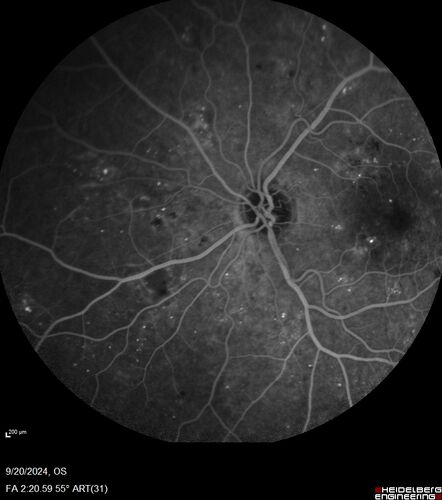

Severe NPDR

53 year old man with blurred vision (needs glasses).

Diabetic for 10 years with poor control

VA 20/32 OU